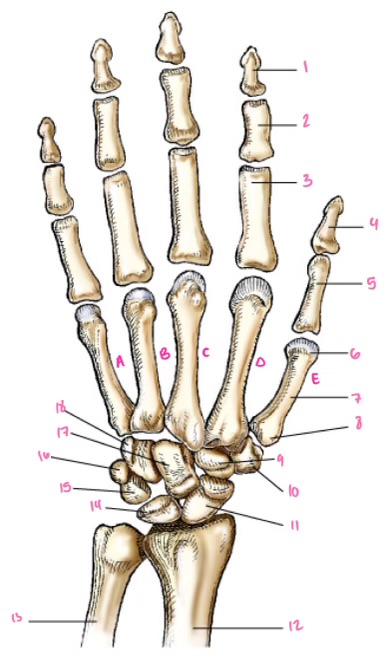

1

1

2

2

3

3

4

9

5

10

6

11

7

14

8

15

9

16

10

17

11

18

12

1

13

2

14

3

15

4

16

5

17

6

18

7

19

8

20

9

7

22

8

23

9

24

10

25

11

26

13

14

15

16

17